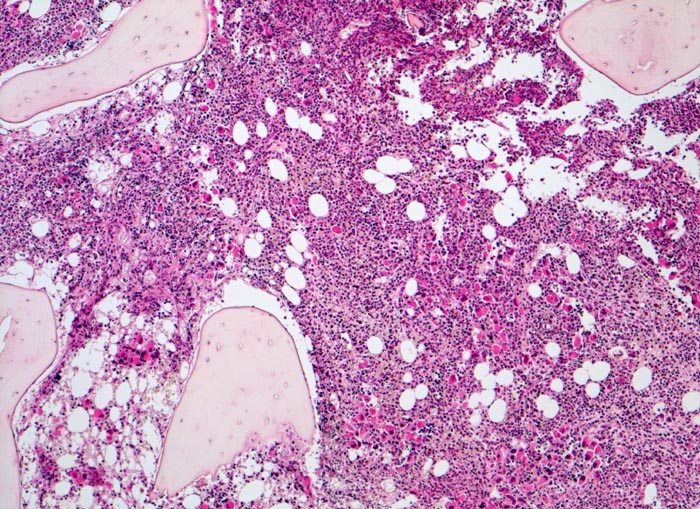

Die Erkrankung ist charakterisiert durch Knochenmarkfibrose, Hepato-Splenomegalie und extramedulläre Blutbildung. Diese findet sich am häufigsten in Leber und Milz, seltener in Lymphknoten, Nieren, Nebennieren, Dura mater, Gastrointestinaltrakt, Lunge, Mamma oder Haut. Blut und Knochenmark sind immer involviert. Die Krankheit entwickelt sich über ein initiales präfibrotisches Stadium mit hyperzellulärem Knochenmark zum fibrotischem Stadium (vorliegendes Präparat). Das fibrotische Stadium ist gekennzeichnet durch eine Vermehrung von Reticulin- und/oder Kollagenfasern und oft einer Knochenneubildung (=Osteomyelosklerose). Die Zellularität des Knochenmarks ist dann vermindert und dilatierte Marksinus enthalten intraluminale Blutbildungsherde. Es besteht eine auffallende Proliferation von Gruppen bildenden atypischen Megakaryozyten.

• Osteosklerose: verplumpte und breite Knochenbälkchen.

• Dilatierte Sinusoide mit intrasinusoidaler Blutbildung.

• Vermehrung von atypischen, in Gruppen liegenden Megakaryozyten mit abnorm lobulierten Kernen.

• Hyperplastische ausreifende Myelopoese.

• Hypoplastische Erythropoese.